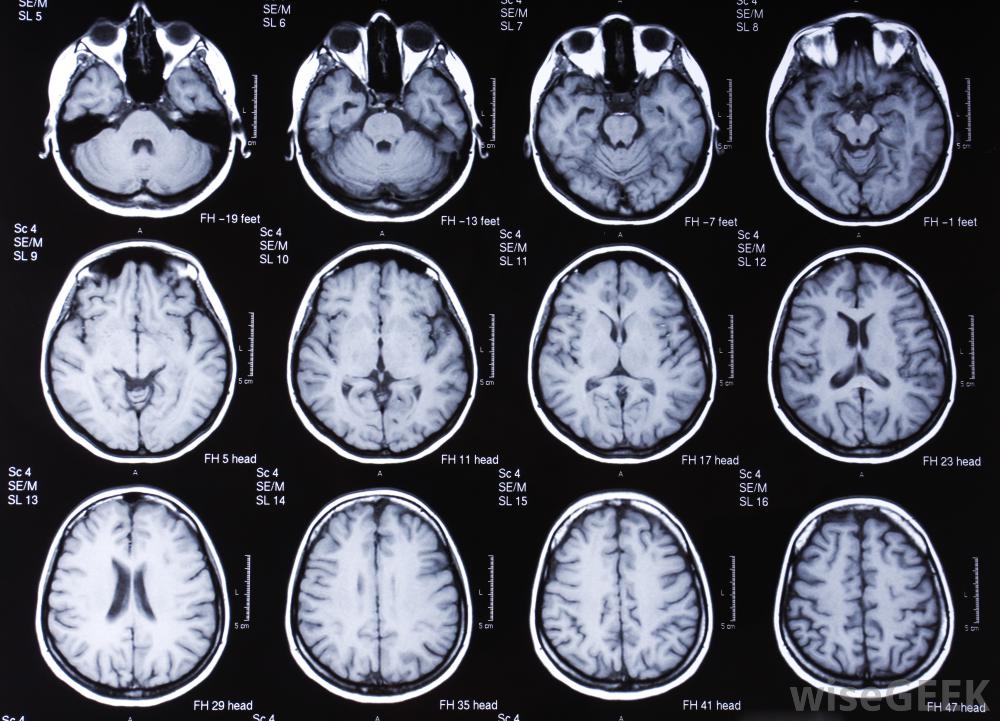

硬腦膜下血腫是一種血液在硬腦膜下的積聚,硬腦膜是大腦的外層,當連接大腦表面和硬腦膜之間的橋靜脈開始滲漏或出血時,就會出現這種情況,慢性硬膜下血腫是指血液在21天前開始積聚,另一種最常見的硬膜下血腫是在72小時前開始出血的急性硬膜下血腫意識不清和記憶力減退是硬膜下血腫的可能征象受年齡、生活方式、近期創傷適應癥和病史等因素的影響,患者的各種癥狀可能會有所不同。慢性硬膜下血腫的許多癥狀與其他情況下的癥狀非常相似。癥狀可能包括焦慮、抑郁、記憶力減退和意識混亂,經常模仿癡呆癥的癥狀。癲癇發作和持續性頭痛也很常見。頭部的MRI掃描可以幫助診斷慢性硬膜下血腫許多癥狀都會導致額外的并發癥。例如,有這種情況的人可能會有吞咽困難,這可能會導致窒息和誤吸四肢無力會導致行動不便,并增加跌倒和進一步受傷的風險。意識混亂和精神狀態改變會導致判斷能力差,增加受傷和決策失誤的風險。慢性硬膜下血腫需要外科手術治療,并且無法自行愈合,因為血液的采集無處可去。治療這種情況的程序被稱為開顱手術。這個過程包括在頭骨上開一個小洞,排出積聚的血液。手術和未經治療的情況都有永久性腦損傷的風險,但慢性硬腦膜下血腫未經治療的風險要大得多。慢性硬膜下血腫通常是由頭部外傷引起的,60歲以上的人更容易發生。作為自然衰老過程的一部分,大腦可能會萎縮或者萎縮,意味著大腦表面變小,硬腦膜和腦表面之間的間隙變大,然后橋靜脈被拉緊,受到更大的力,即使是輕微的頭部外傷,也會造成更大的滲漏和血腫形成的威脅服用抗凝血藥物的人患慢性硬膜下血腫的風險增加,因為如果橋靜脈開始滲漏,血液無法有效地凝結。在嬰兒中,硬膜下血腫通常是由創傷或虐待引起的,如嬰兒搖晃綜合征。其他人發生慢性硬膜下血腫的高風險包括長期酗酒和濫用藥物慢性硬膜下血腫患者吞咽困難,可能導致窒息。